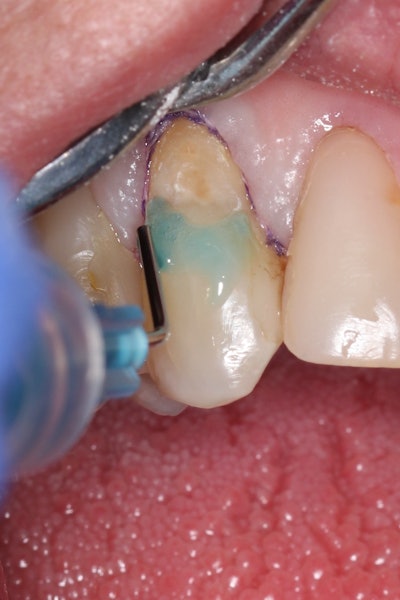

The tooth was evaluated using a caries indicator dye (Kuraray Noritake Dental), helping to identify any remaining infected tissue beneath the dislodged composite (Figure 3).

Figure 3: Application of caries indicator dye to identify remaining infected tissue beneath the dislodged composite.Figure 3: Application of caries indicator dye to identify remaining infected tissue beneath the dislodged composite.